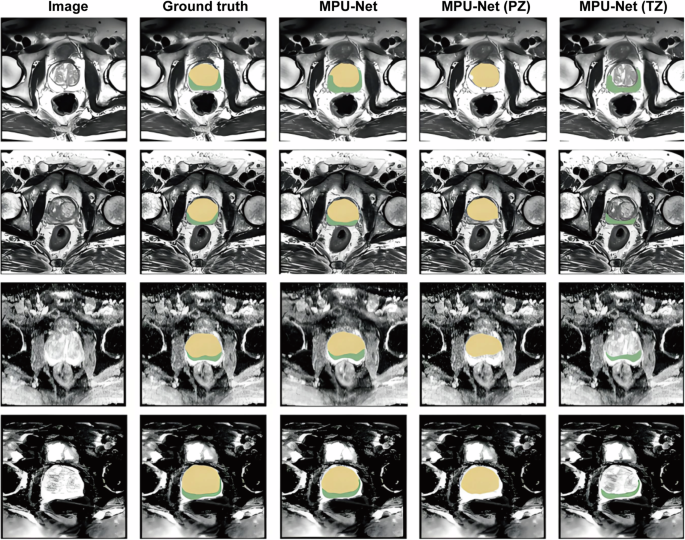

The prostate is divided into the Peripheral Zone (PZ), Transition Zone (TZ), and Central Zone (CZ). 70% of PCa originates from PZ, and 30% originates from TZ. However, TZ lesions are more likely to be missed due to their high overlap with BPH images. Traditional manual segmentation requires surgeons to outline MRI images layer by layer, taking about 20 min per case, and the segmentation consistency Kappa value is only 0.5–0.719,20. The deep learning-based segmentation algorithm realizes pixel-level semantic segmentation through an encoder-decoder, significantly improving the efficiency and accuracy of segmentation, as shown in Fig. 2.

The first column is the prostate image, the second column is the ground truth of the prostate, the third column is the segmentation result of MPU-Net, the fourth and fifth columns are the PZ and TZ segmented by MPU-Net, respectively. The four rows of images represent four different cases. The first two rows show MRI modality, and the last two rows show ADC modality. Both modalities are used in the actual segmentation process. MPU-Net Morphology-Preserving U-Net, PZ Peripheral Zone, TZ Transition Zone, MRI Magnetic Resonance Imaging, ADC Apparent Diffusion Coefficient.

Chen constructed a U-Net++ model using 1000 cases of mp-MRI, using residual connections to avoid gradient disappearance in deep networks and a Dice loss function to optimize segmentation boundaries. The Dice Similarity Coefficient (DSC) of this model for the entire prostate, PZ, and TZ was significantly higher than that of the classic CNN model, and the segmentation time for a single case was only 1.2 min21,22. In addition, the model maintained robustness to datasets of MRI with different field strengths, well solving the problem of model inapplicability caused by image differences generated by different devices. In 2023, Zhao et al. added an attention gating module to the above model, and by improving the feature extraction ability for TZ boundaries, the segmentation DSC of TZ reached 0.90. The TZ area segmented by AI is the basis for accurate segmentation of TZ lesions—clinical reports show that based on radiomic analysis of the TZ area segmented by AI, the detection rate of TZ PCa is increased by 20–30%.